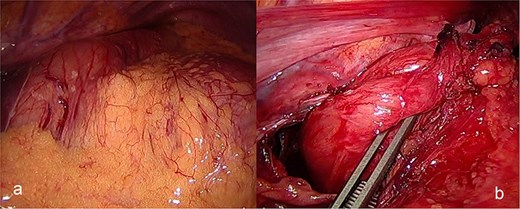

The patient was admitted under the care of the general surgery department, and he was taken to the operating room for a laparoscopic exploration, which showed mesenteroaxial gastric volvulus, wandering spleen, and a large hiatal hernia which was ~5 cm in size. No devitalized tissues were found. An attempt at intraoperative endoscopy failed to pass through the hiatus. A cruroplasty with a Toupet fundoplication and gastropexy were done as shown in (Figs 3 and 4). On the third postoperative day, the patient was doing well. He was tolerating oral intake and passing regular motions and was discharged home in good condition as he was traveling to his country.

(a) The spleen appears healthy and in an abnormally mobile position, consistent with a wandering spleen, with absent or lax ligamentous attachments. (b) Postreduction view of the stomach, with its body sutured to the lateral abdominal wall (gastropexy) to prevent recurrence of mesenteroaxial gastric volvulus.